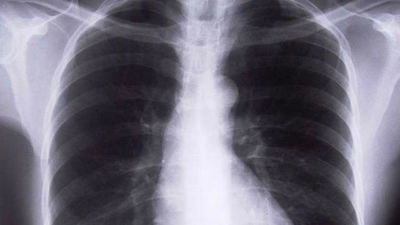

El Hospital de Móstoles usa una nueva técnica para detectar el cáncer de pulmón El Hospital de Móstoles usa una nueva técnica para detectar el cáncer de pulmón 07/06/2023

Los hospitales cribarán el cáncer de pulmón mediante un TAC en una prueba piloto Los hospitales cribarán el cáncer de pulmón mediante un TAC 24/04/2023

Investigadores españoles hallan el ‘talón de Aquiles’ cáncer de pulmón en la inhibición de una proteína Investigadores españoles hallan el ‘talón de Aquiles’ cáncer de pulmón en la inhibición de una proteína 21/11/2022